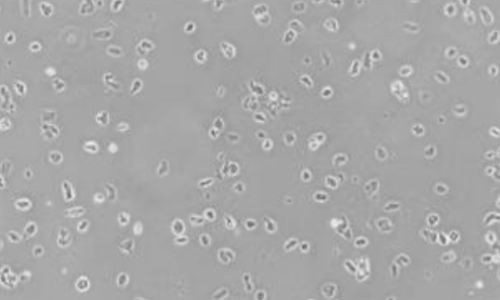

▲人食管癌 FFPE 样本 |